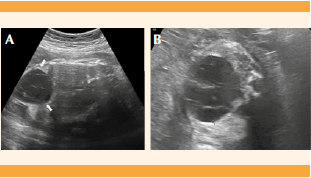

Paciente de 21 años, primigesta, sin antecedentes patológicos ni ginecoobstétricos relevantes para el padecimiento actual, valorada en el servicio de Medicina Materno Fetal con reporte de embarazo único vivo, de 15.2 semanas, por fetometría, sin alteraciones estructurales fetales, con placenta corporal anterior, de morfología anormal, con múltiples imágenes hipoecogénicas que semejan racimos de uvas, sin flujo vascular en el Doppler color (Figura 1) que pudiera corresponder a degeneración hidrópica, por eso se sospechó enfermedad trofoblástica gestacional de tipo mola hidatiforme parcial.

Figura 1 (A, B).Imagen ecográfica que muestra una placenta corporal anterior engrosada con múltiples imágenes hipoecogénicas que semejan racimos de uvas en un embarazo de 15 semanas (flechas). (C) Misma placenta a las 33 semanas de gestación con lesiones quísticas ecogénicas (flechas) compatibles con displasia mesenquimal placentaria corroborada por histopatología al nacer.